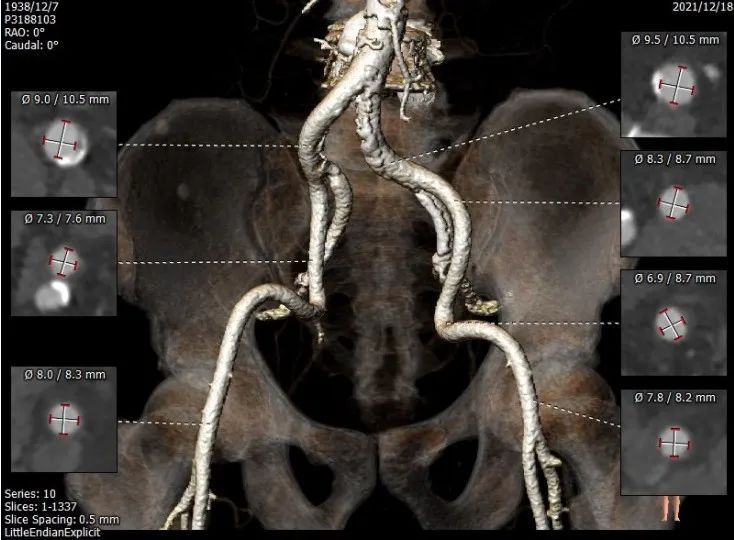

股动脉入路

对于纯反流的病例,在决定是否可行TAVR时,需要对主动脉根部的结构进行详细的分析及测量。这个病例中,需要Oversize选择VitaFlow Liberty™ TAV30型号的瓣膜, 能够对瓣膜提供锚定功能的锚定区——瓣环、左室流出道、升主动脉、STJ,预估选择TAV30的瓣膜锚定点能够提供足够的锚定力。

张俊杰教授的观点是首先AR患者Oversize比例自膨瓣是根据周长来选择。AR患者瓣上没有锚定区,需要一定程度的Oversize,否则有出现延迟掉入左室流出道的风险,VitaFlow Liberty™ 的电动可回收功能带给术者更多的信心去释放,这个患者结合术前的CT分析,流出道直筒装有较易锚定的解剖结构,瓣环下4—5mm 处可以进行释放。患者升主动脉直径38mm, 30号 VitaFlow® 瓣膜打开花冠直径43mm可提供有效锚定。瓣膜植入时,VitaFlow® 瓣膜释放到 75% ,可以停下来观察,通过轻推导丝使瓣膜同轴,如果有移位现象可以回收重新释放甚至可以撤出换一个型号。